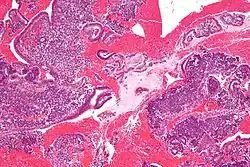

Micrograph of decidualized endometrium due to exogenous progesterone. H&E stain.

Micrograph of decidualized endometrium due to exogenous progesterone. H&E stain. -

Micrograph of decidualized endometrium due to exogenous progesterone. H&E stain.

Micrograph of decidualized endometrium due to exogenous progesterone. H&E stain. -